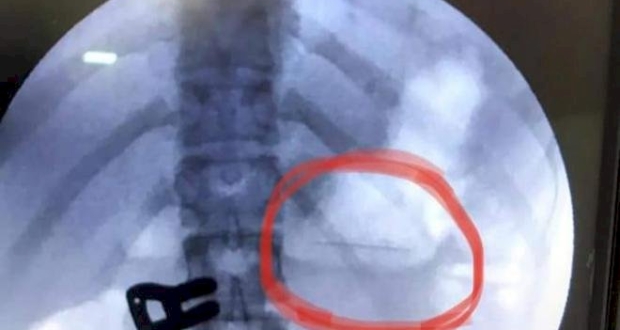

وأوضح الشاعر أن المريضة حضرت الي قسم المناظير بعد ابتلاعها لدبوس، وأجريت لها صورة الأشعة وتبين أن الدبوس عالِق في المعدة، وقد أجريت لها على الفور عملية منظار للمعدة واستخراج الدبوس بعناية تامة دون تعرّض المريضة لمضاعفات أثناء استخراجه وذلك لعدم توفر الامكانيات المناسبة لمثل هذه العمليات بسبب النقص الحاد في مستلزمات المناظير استطاعت المريضة مغادرة قسم المناظير بعد ساعة من اجراء العملية وهي بصحة جيدة.

غزة: استخراج دبوس بطول 2سم بالمنظار من معدة فتاة